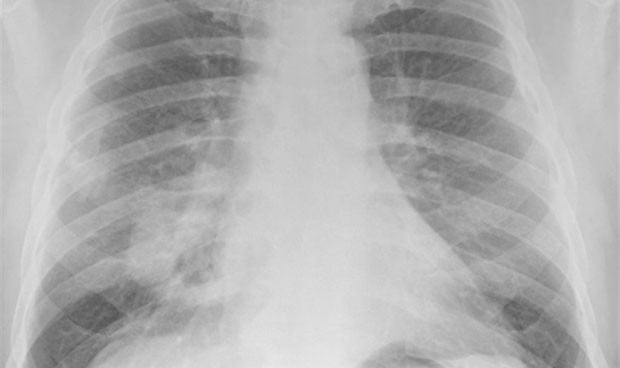

Un  estudio ha identificado un nuevo subtipo agresivo de carcinoides pulmonares, llamados supracarcinoides. Se trata de un tipo de cáncer de pulmón poco estudiado y que hasta ahora no parece estar relacionado con el tabaquismo. El trabajo se ha publicado en la revista Nature Communications y ha sido dirigido por la Agencia Internacional para la Investigación del Cáncer (IARC), un órgano intergubernamental que forma parte de la Organización Mundial de la Salud.

En el estudio, en el que han participado dos investigadores del Instituto de Investigación Sanitaria La Fe (IIS La Fe), se han identificado este subtipo utilizando tecnologías de secuenciación innovadoras que proporcionan información sobre las características moleculares de los tumores